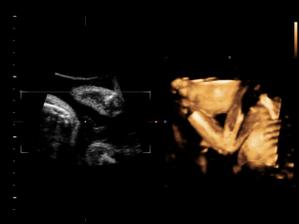

Náš pokladík v brušku

Naše chlapčiatko v 27tt+3...